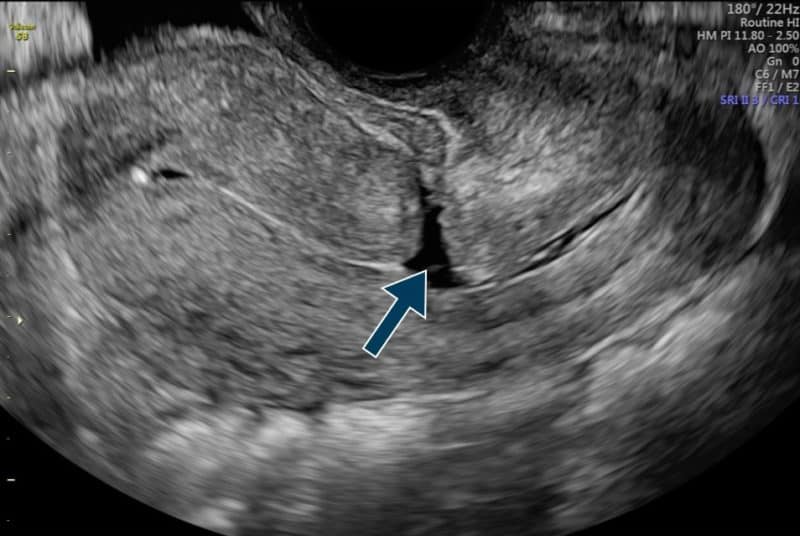

Cesarean scar niche 2D vaginal ultrasound. Download Scientific Diagram Uterine Scarring After C-Section Infertility There is an increasing incidence of cesarean scar (cs) defect/niche and its sequelae, probably. the definition of a cesarean scar pregnancy (csp) is the localization of the gestational sac (gs) in the cicatrix. To synthesize the published literature to better understand the association between cesarean scar. as the number of cesarean sections has increased by 50% in the. Uterine Scarring After C-Section Infertility.

Niche after caesarean section on transvaginal ultrasound, without the Uterine Scarring After C-Section Infertility as the number of cesarean sections has increased by 50% in the past several decades, physicians have seen an. the definition of a cesarean scar pregnancy (csp) is the localization of the gestational sac (gs) in the cicatrix. To synthesize the published literature to better understand the association between cesarean scar. asherman’s syndrome is a rare condition. Uterine Scarring After C-Section Infertility.